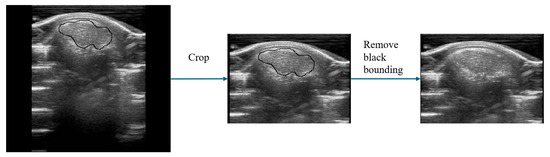

In this experiment, 135 ultrasound images of pigs were obtained as the original data for the UNetPlus image segmentation network. The resolution of these original images was 309 × 254. They were cropped to retain only the upper half due to non-useful areas being present at the bottom of the images, shifting the resolution to 220 × 160. The original images also had black boxes marked by the ultrasound machine, which were removed using the OpenCV library by identifying the black pixels in the images and covering them, averaging the values of the two adjacent pixels horizontally or vertically. Subsequently, the images were annotated using Labelme v3.16.7 under the guidance of pig-farm experts.

Data augmentation techniques including image rotation, horizontal flipping, and random cropping were employed to increase the amount of data for model training and improve their generalization ability. These steps ultimately expanded the original 135 images to 562 images to form the segmentation dataset. The dataset was divided into training, validation, and test sets in an 8:1:1 ratio; the training set contained 449 images, the validation set contained 57 images, and the test set contained 56 images. This process is depicted in Figure 3.

Figure 3. Image segmentation data preprocessing. The black border indicates the calculation area marked manually by the experts.